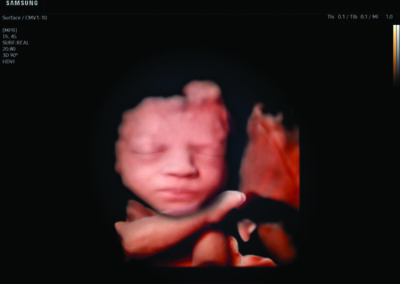

Comprehensive, advanced and expert MFM care for high-risk pregnancies

- Fetal anomalies